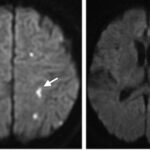

Se pueden mencionar al respecto los estudios que han encontrado en pacientes dependientes al alcohol una disminución del volumen de sustancia gris en el área de la corteza frontal, el hipocampo y el tálamo. El volumen de las sustancias blanca y gris también se puede ver disminuido en el área periventricular, la protuberancia y el cerebelo. Estos déficits de volumen también se han localizado en la corteza prefrontal dorsolateral derecha, ínsula anterior derecha, en el núcleo accumbens y en la amígdala izquierda(16) (ver Imagen 1).

Asimismo, como se indicó previamente, a través de la TC también se puede observar el deterioro de la microestructura cerebral por adicción al alcohol. El abuso de esta sustancia altera cinco fibras del cerebro, como el cuerpo calloso, el fondo de saco, la cápsula externa, el cíngulo circunvolución y el fascículo longitudinal superior, las que están involucradas en funciones como el procesamiento visoespacial y del lenguaje, la comunicación interhemisférica, la memoria, el procesamiento emocional, la toma de decisiones y la integración sensorial(16) (ver Imagen 2).